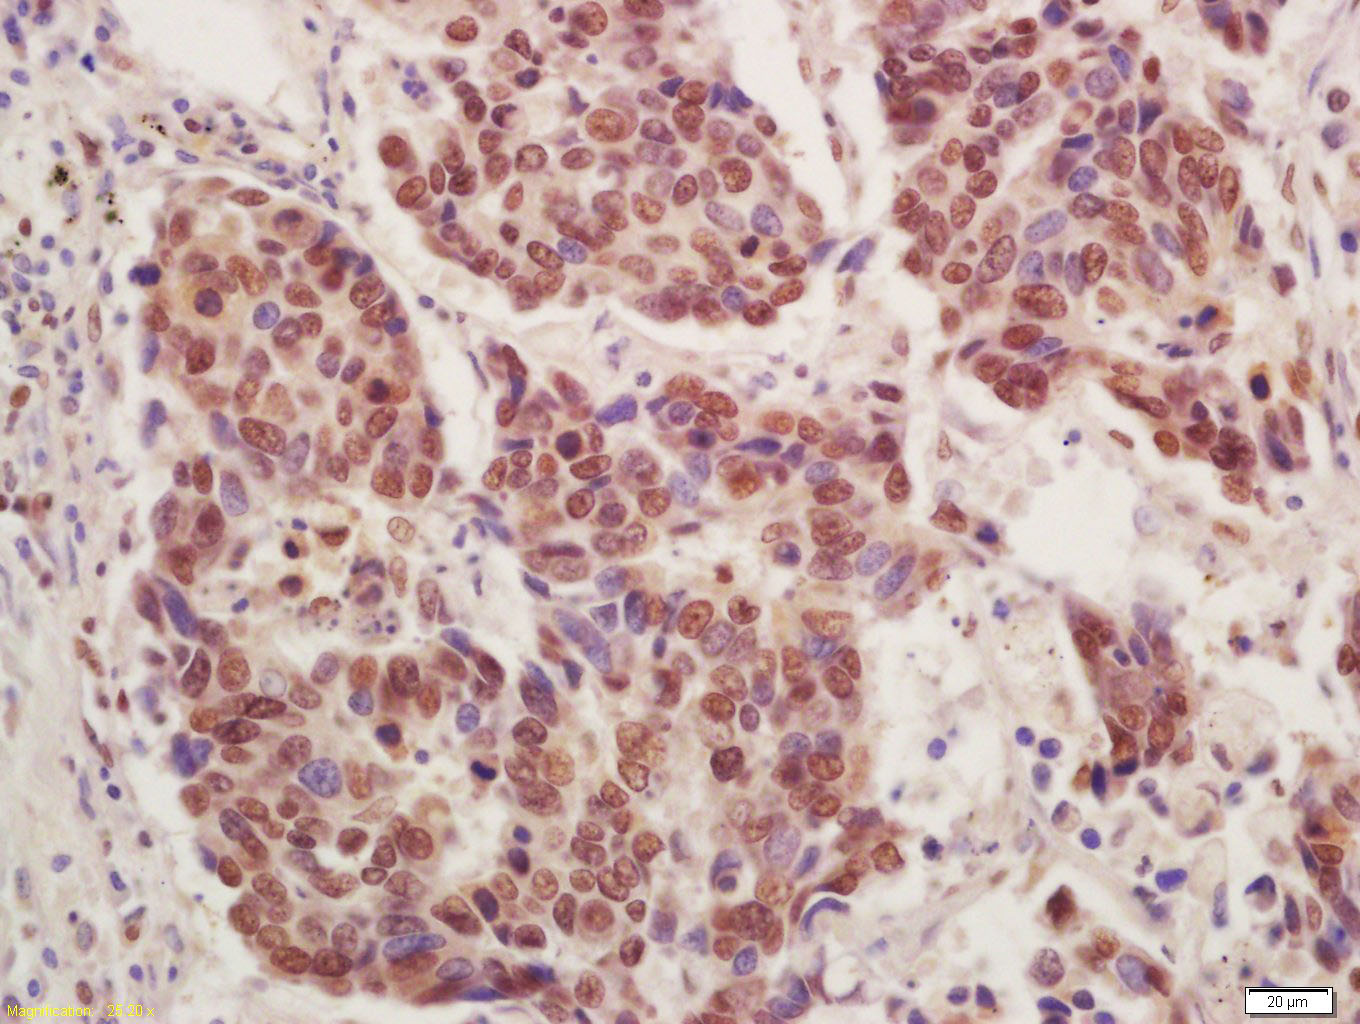

Tissue/cell: human lung carcinoma; 4% Paraformaldehyde-fixed and paraffin-embedded; Antigen retrieval: citrate buffer ( 0.01M, pH 6.0 ), Boiling bathing for 15min; Block endogenous peroxidase by 3% Hydrogen peroxide for 30min; Blocking buffer (normal goat serum,C-0005) at 37℃ for 20 min; Incubation: Anti-CT112 Polyclonal Antibody, Unconjugated(bs-8313R) 1:200, overnight at 4°C, followed by conjugation to the secondary antibody(SP-0023) and DAB(C-0010) staining

Paraformaldehyde-fixed, paraffin embedded (Rat testis); Antigen retrieval by boiling in sodium citrate buffer (pH6.0) for 15min; Block endogenous peroxidase by 3% hydrogen peroxide for 20 minutes; Blocking buffer (normal goat serum) at 37°C for 30min; Antibody incubation with (Cancer/testis antigen 112; CT112) Polyclonal Antibody, Unconjugated (bs-8313R) at 1:400 overnight at 4°C, followed by a conjugated secondary (sp-0023) for 20 minutes and DAB staining.